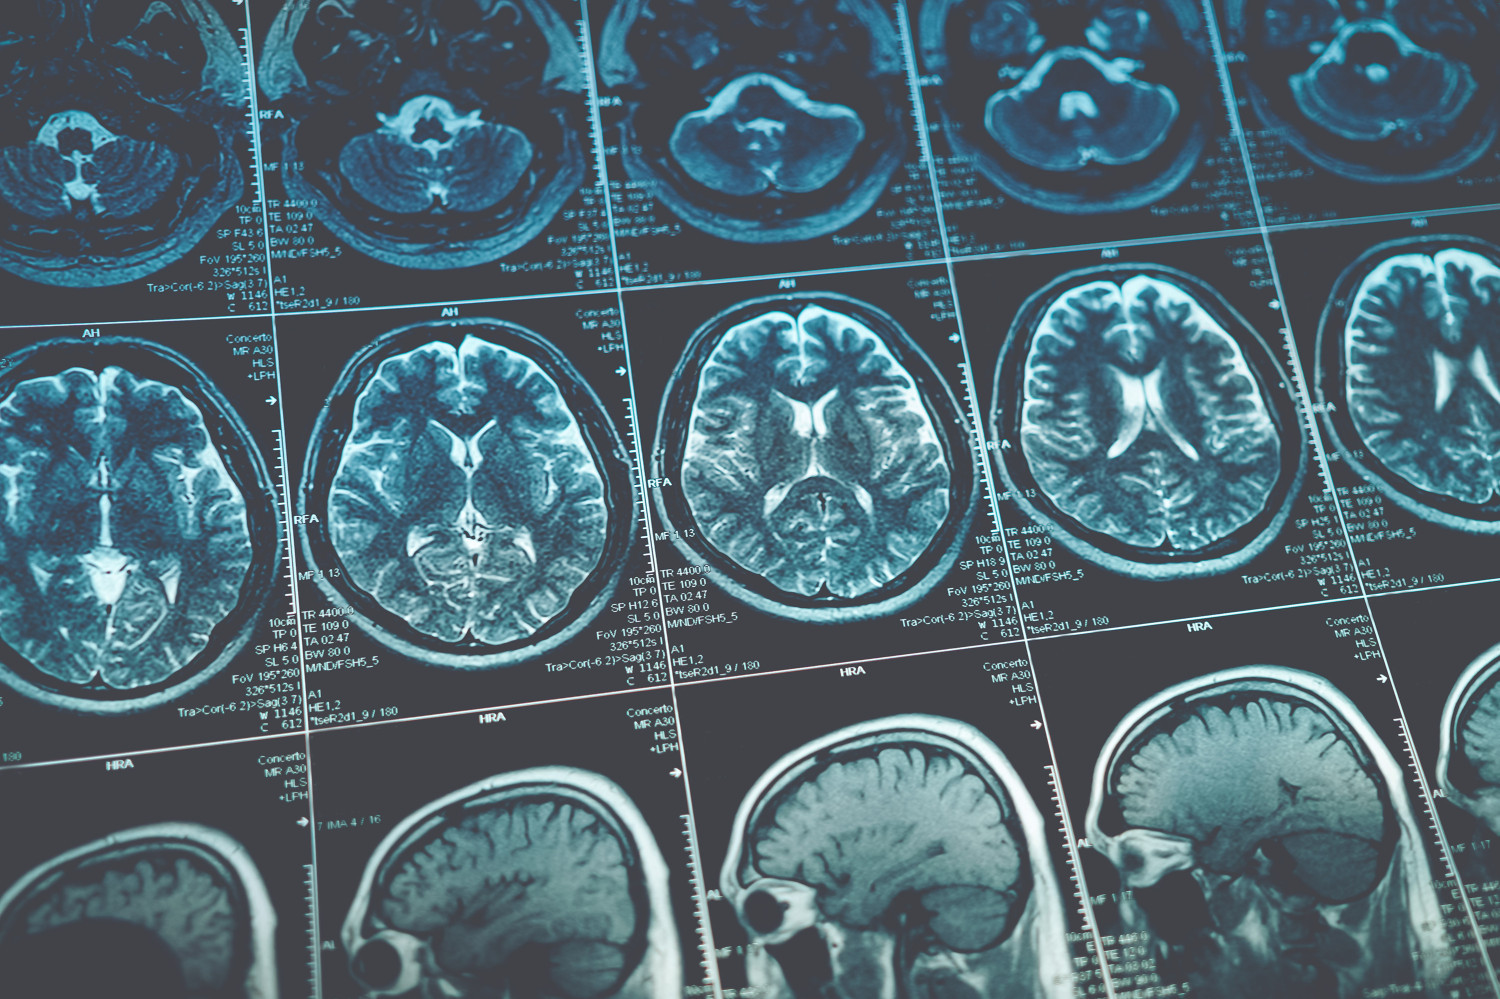

| Анализировали данные 426 пациентов с острым ишемическим инсультом, которым не проводили тромболизис или эндоваскулярную тромбэктомию. Их разделили на две группы: одним внутривенно вводили тирофибан, а другие получали традиционную пероральную терапию аспирином. Оценивали риск развития ранних неврологических нарушений и ухудшение неврологического состояния в течение 72 часов после рандомизации. Для оценки безопасности определяли частоту развития симптоматических внутримозговых кровоизлияний и системных кровотечений. |

Анализ показал, что ранние неврологические нарушения встречались у 13,2% пациентов, которым назначили аспирин, по сравнению с 4,2% участников в группе тирофибана. Ухудшение неврологического состояния в течение 72 часов также реже встречалось в группе тирофибана по сравнению с группой аспирина: в 11,7 и 23,6% случаев.

В течение 72 часов после начала лечения ни в одной из групп не было выявлено симптоматических внутримозговых кровоизлияний. Частота системных кровотечений также существенно не различалась между группами.